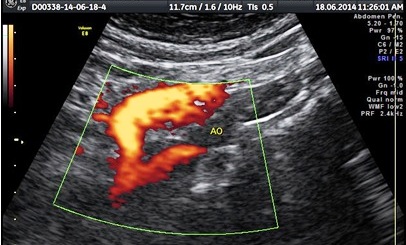

Pregnancy sonography | Anomalies scan | NT scan | fetal echocardiography | Chembur Powai